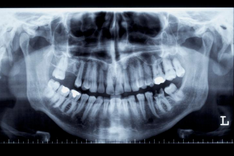

임플란트 가격 시술과정 등 정보에 대해 알아보도록 하겠습니다. 임플란트는 손상된 이빨이나 빈 치아를 대체하기 위한 인공 이빨입니다. 일반적으로 작은 나사 모양의 금속 장치로, 잇몸과 안면골 사이에 삽입됩니다. 이 장치는 실제 이빨과 동일한 역할을 수행하고, 씹기, 말하기 및 웃음을 할 때 자연스러운 모습을 유지합니다.

임플란트의 주요 재료는 티타늄이며, 이는 인체 내에서 잘 흡수되는 재료입니다. 티타늄 재질은 뼈와 잘 결합되어 안정성을 높이며, 인공 이빨을 장기간 사용할 수 있도록 해줍니다.

임플란트 수술은 전문적인 치과 의사나 구강 외과 전문의에 의해 수행됩니다. 일반적으로 수술 후 임플란트는 몇 개월 동안 치아와 함께 인공 잇몸으로 덮여 골이 잘 결합되도록 하고, 그 후에 인공 이빨이 부착됩니다.